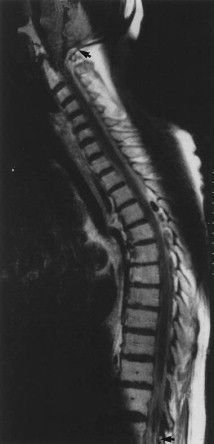

Diseases of various organ systems can give rise to backache. Following are the condition that can present with back pain: Cardiovascular system: Abdominal aortic aneurysm Respiratory system: Mesothelioma Gastrointestinal system: Pancreatitis or peptic ulcer disease Genitourinary system: Tumors of prostate, ovaries, or testes; pyelonephritis Reference: Bailey and Love's Short Practice of Surgery Image via: https://www.sciencedirect.com/science/article/pii/S0022522302000661